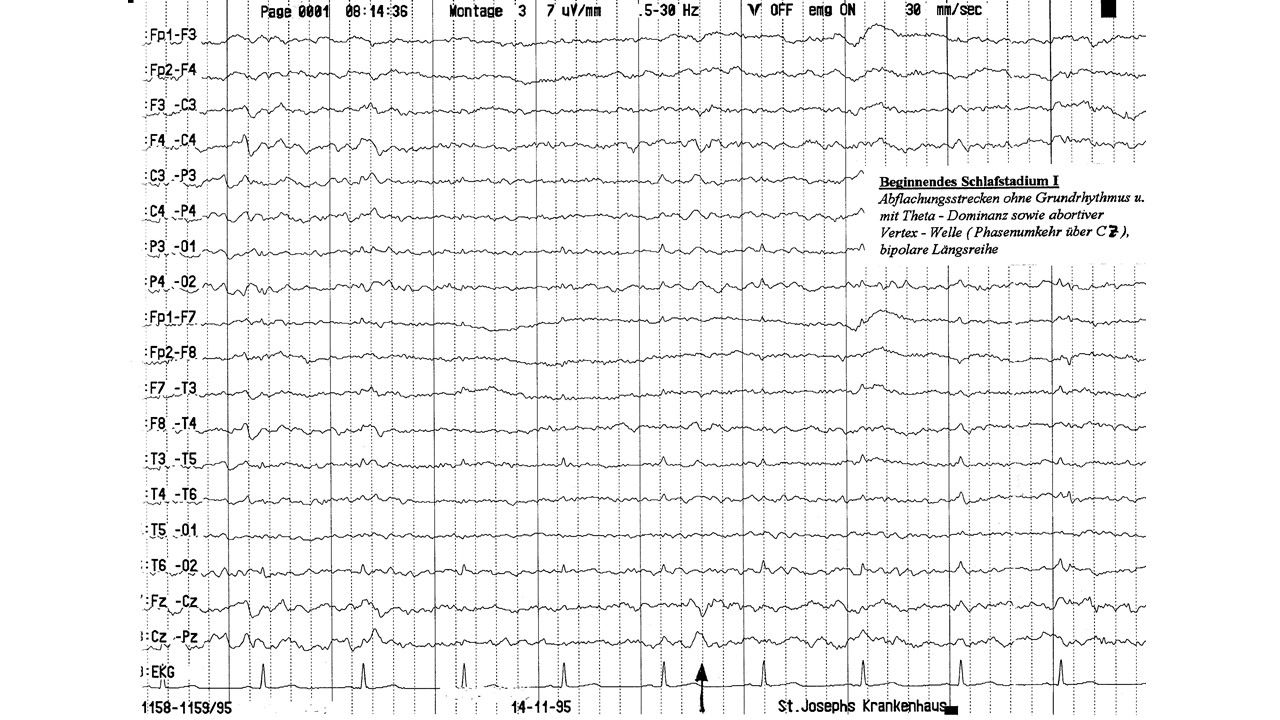

folie70.jpg